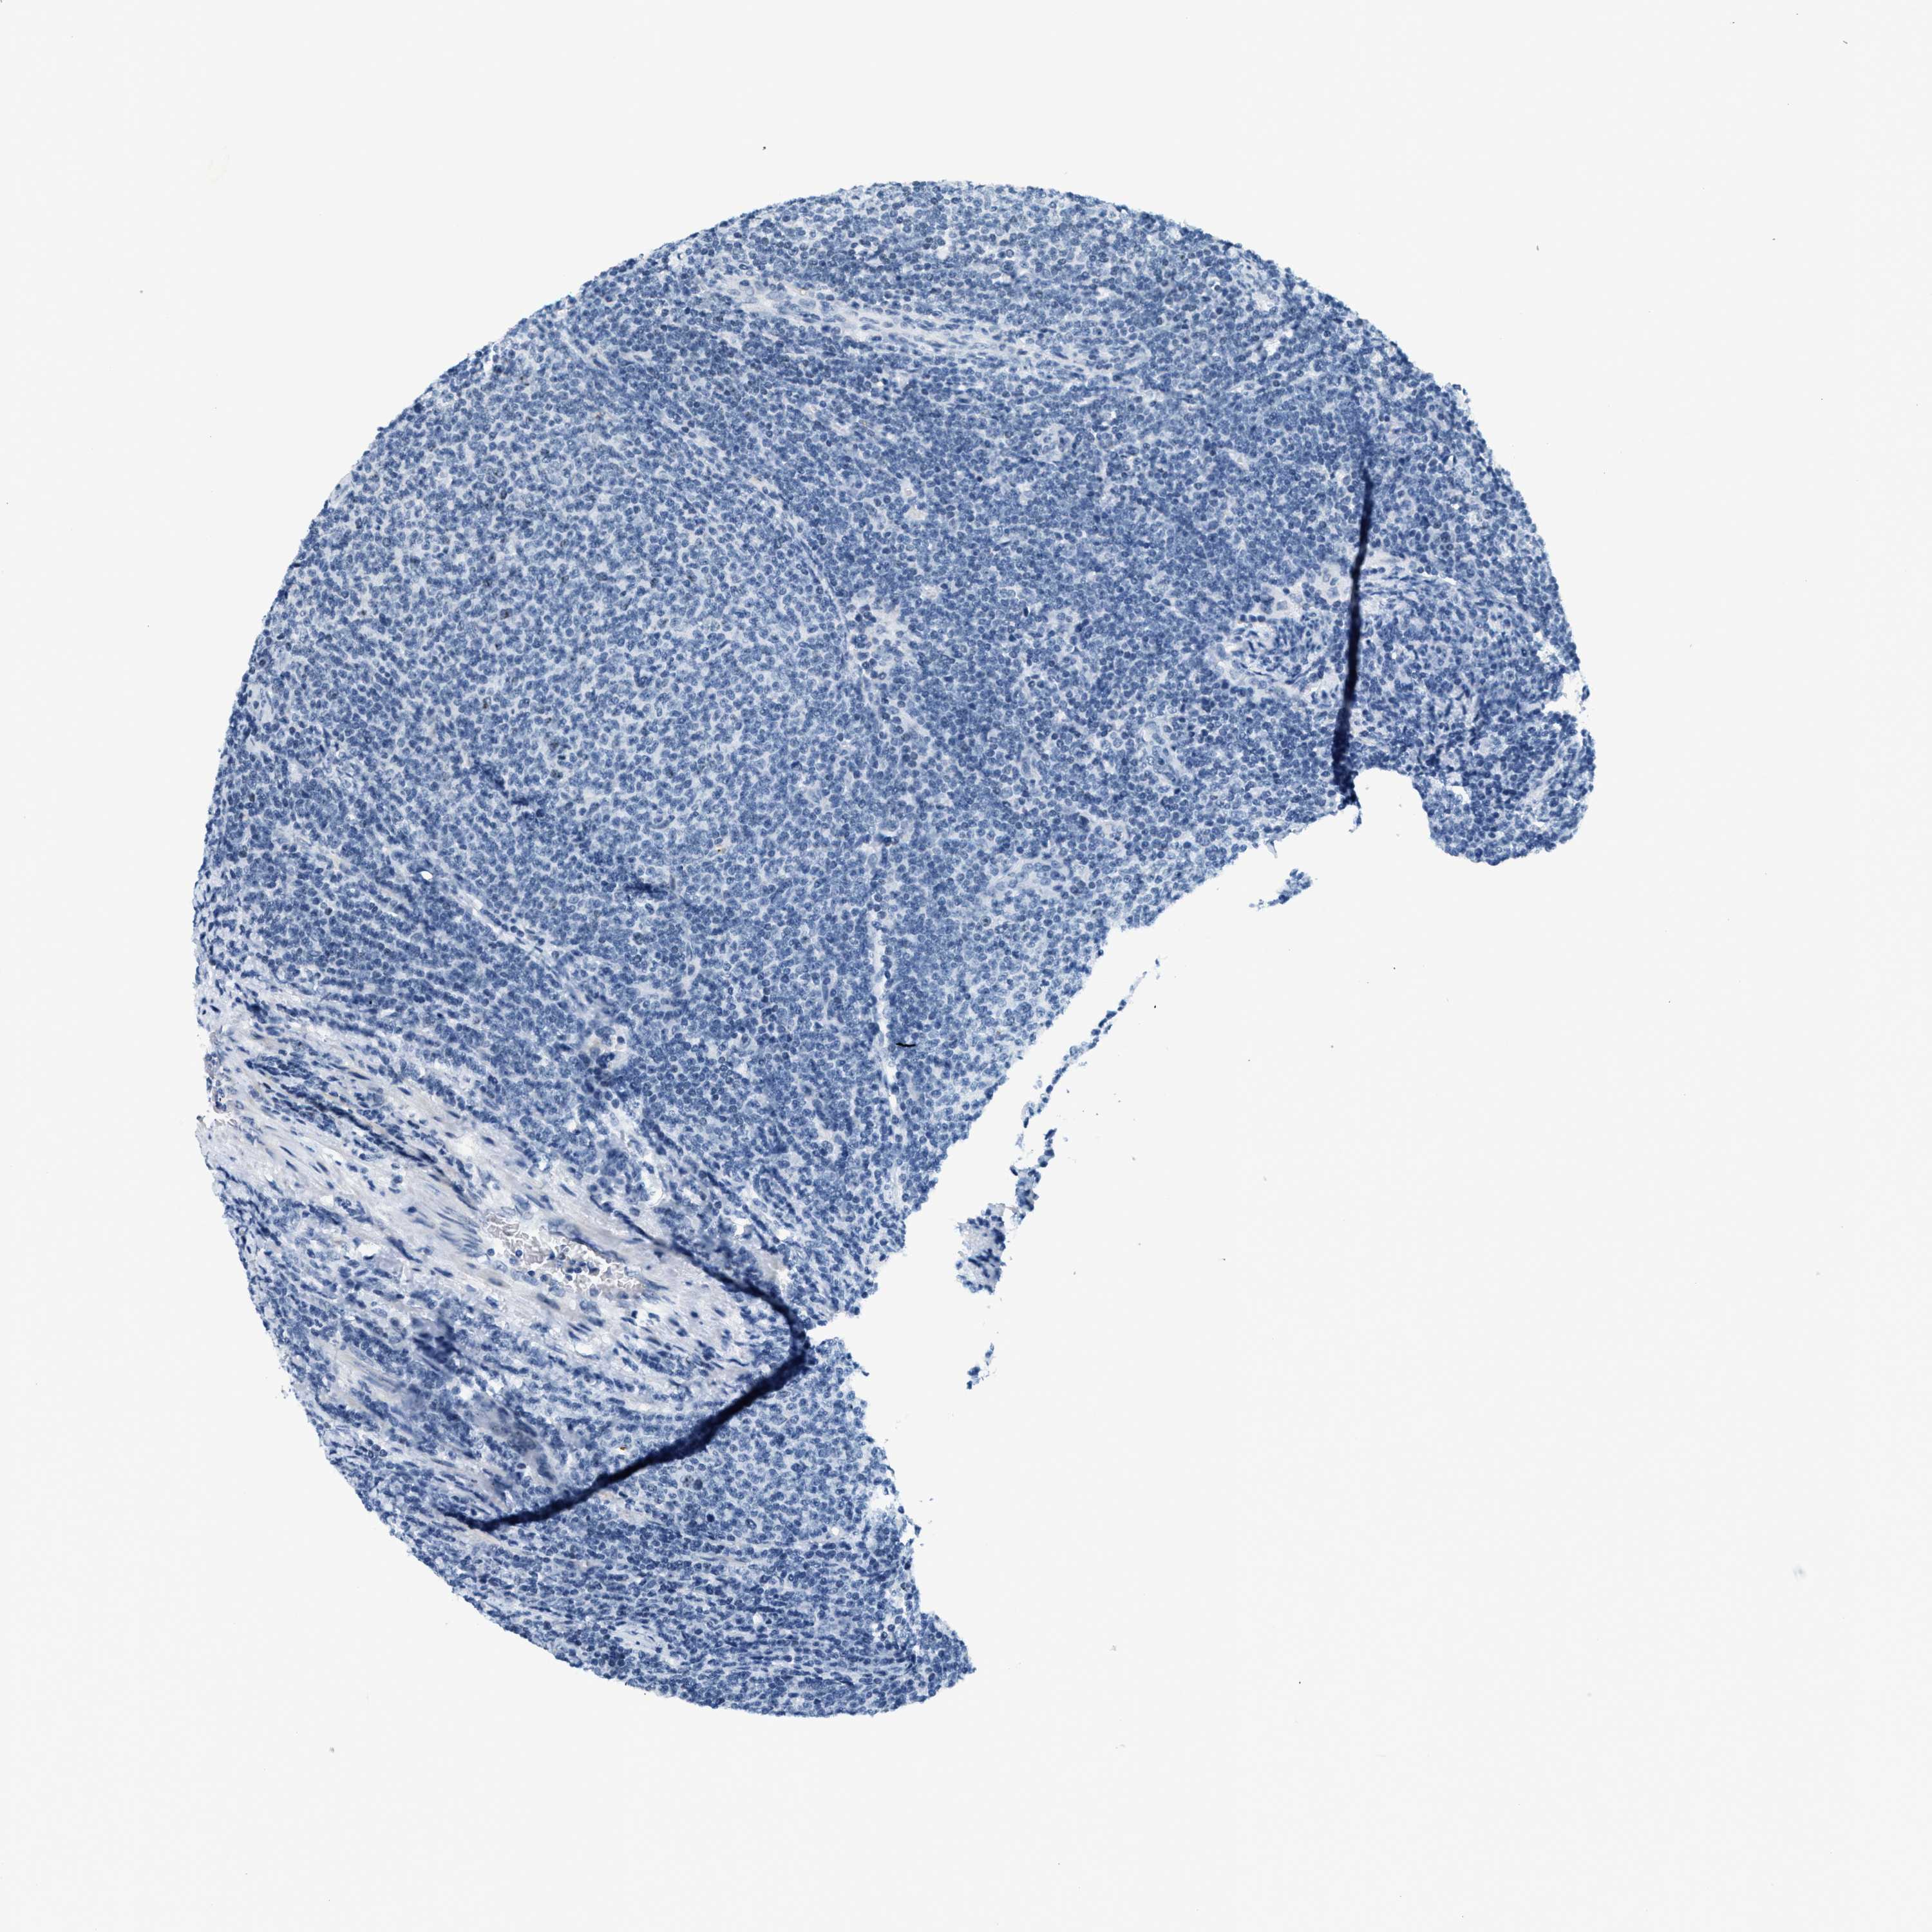

CANCER LYMPHOMA Show tissue menu

LYMPHOMA - Protein expressioni

A mouse-over function shows sample information and annotation data. Click on an image to view it in a full screen mode. Samples can be filtered based on level of antibody staining by selecting one or several of the following categories: high, medium, low and not detected. The assay and annotation is described here.

Each image is clickable and will lead to virtual microscopy that enables deeper exploration of all samples and also displays staining intensity scores, fraction scores and subcellular localization as well as patient and tissue information for each sample.

Antibody HPA014855

Staining

High

Medium

Low

Not detected

Intensity

Strong

Moderate

Weak

Negative

Quantity

>75%

75%-25%

<25%

None

Location

Nuclear

Cytoplasmic/membranous

Cytoplasmic/membranous,nuclear

Hodgkin's disease, NOS

Malignant lymphoma, non-Hodgkin's type, High grade

Malignant lymphoma, non-Hodgkin's type, Low grade